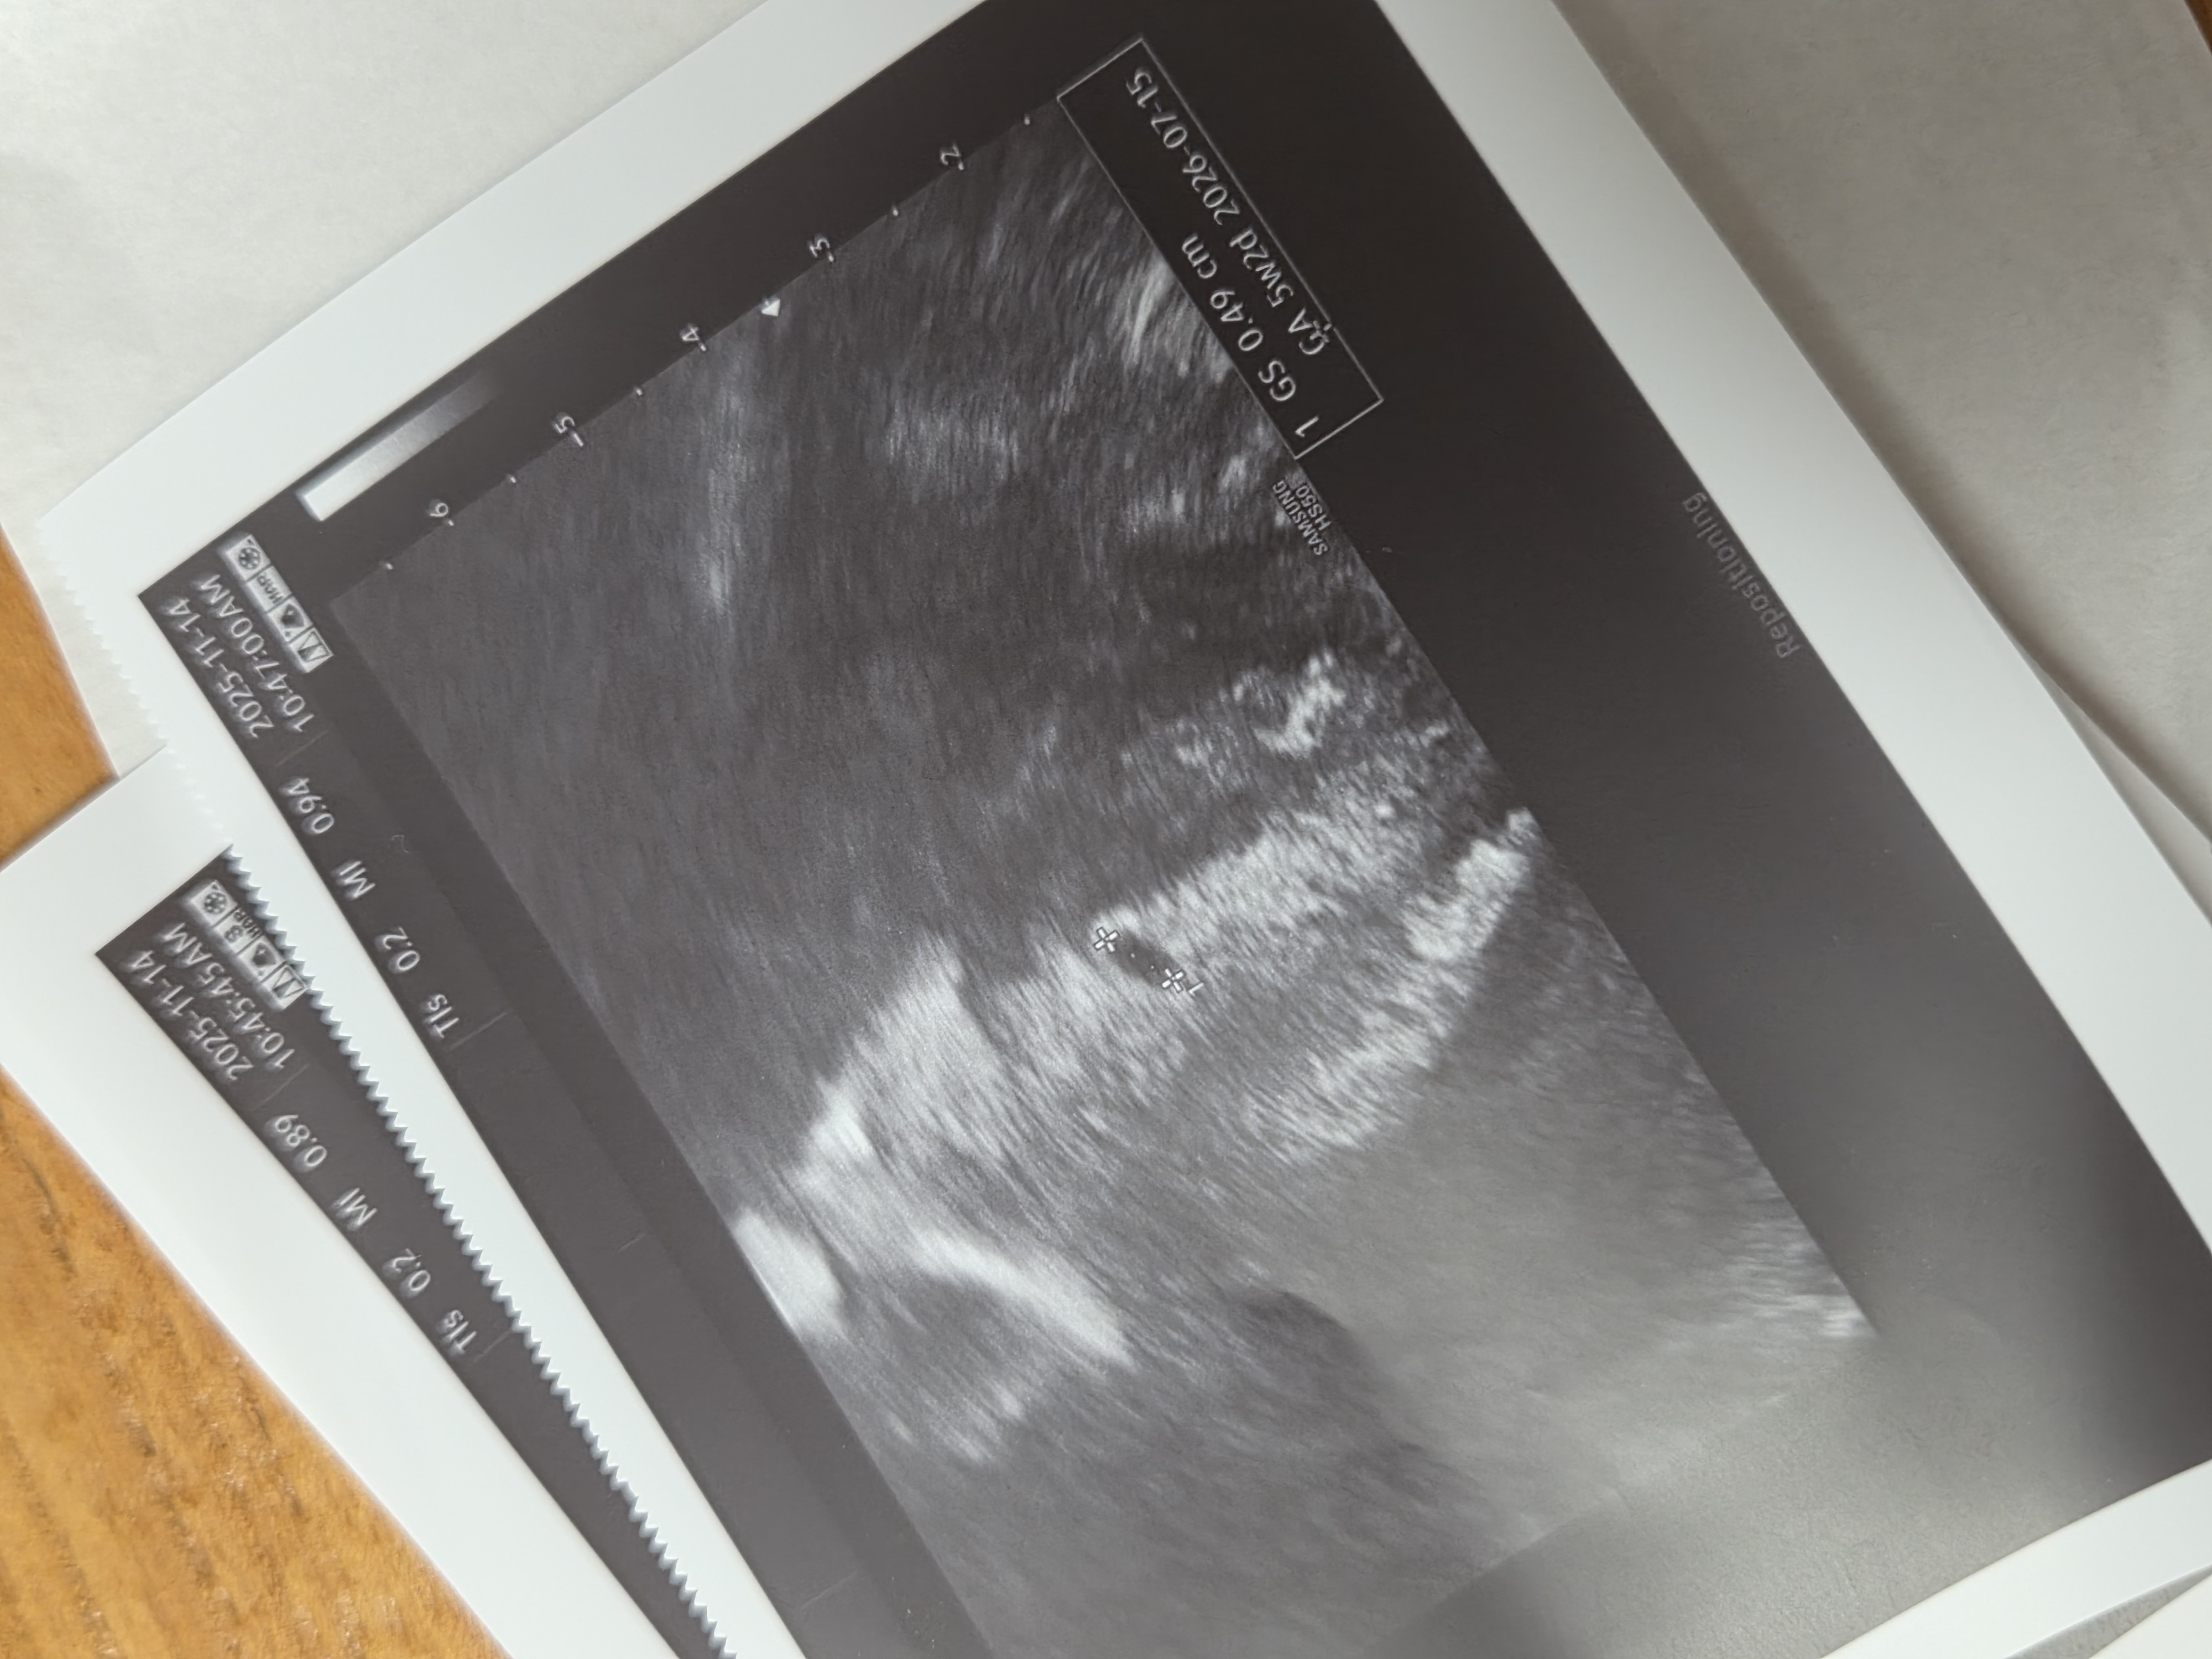

네이버 주수 기준으로는 5주 1일 (배란 18일차) 엊그제 원포 임테기로 역전했길래 못 참고 다녀왔어요 처음엔 질초음파로 했는데 안 보인다 그래서ㅠㅠ 피검사 했는데 4500 정도 나와서 다시 배랑 질초음파 봤더니 아주 쪼끄맣게 보이네요ㅎㅎ 크기 기준으로는 5주 2일차라는데 아기집 크기 4.9mm 나쁘지 않은건가요?